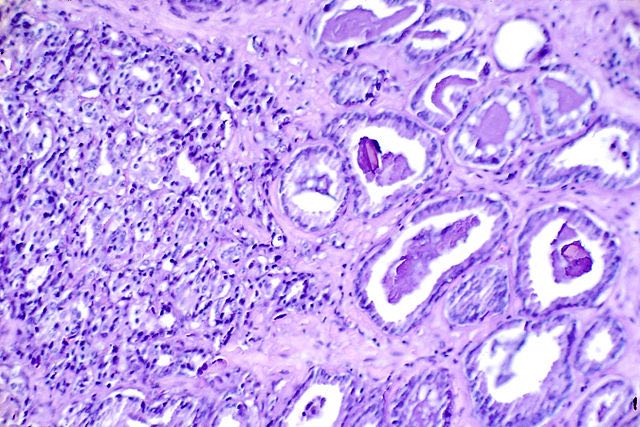

Kazmierczak and the team at the Cancer Research Center at MU developed ‘CRC2631’, a Salmonella strain that has been genetically modified to render the bacteria nontoxic and enhance its natural ability to target and kill cancer cells—without harming normal, healthy cells. The Salmonella strain was administered directly into the circulatory system of mice with prostate cancer.

“We found that the mice tolerated the treatment well and when examined, their prostate tumors decreased by about 20 percent compared to the control group,” Kazmierczak said. “One of the most remarkable aspects of Salmonella is its ability to target, spread and persist inside the tumor. We are taking advantage of this ability by using Salmonella to carry or generate effective chemotherapeutic drugs, concentrating them at and throughout the tumor. The goal of this treatment is to develop a bacterial vector that can destroy the tumor from the inside out and reduce the amount of side effects endured by patients with cancer.”